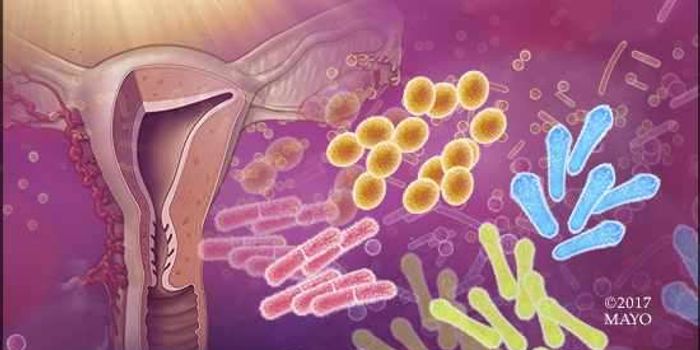

OCT 08, 2017MicrobiologyBacteria live on and in us and have been found to exert a major influence on our health. Researchers want to know about ...

MAR 16, 2016Clinical & Molecular DXThe microbiome is a specialized collection of bacteria residing in the human body. Mostly famous for their existence in ...